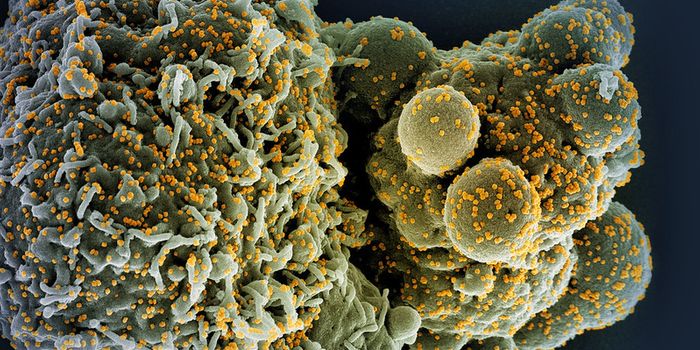

JUL 11, 2021MicrobiologyIn October 2020, what's now called the Delta variant of SARS-CoV-2 was first detected. It's now the most prevalent strai ...

NOV 01, 2021Cell & Molecular BiologyResearchers have learned a lot about the SARS-CoV-2 virus since the start of the COVID-19 pandemic. We know that he viru ...